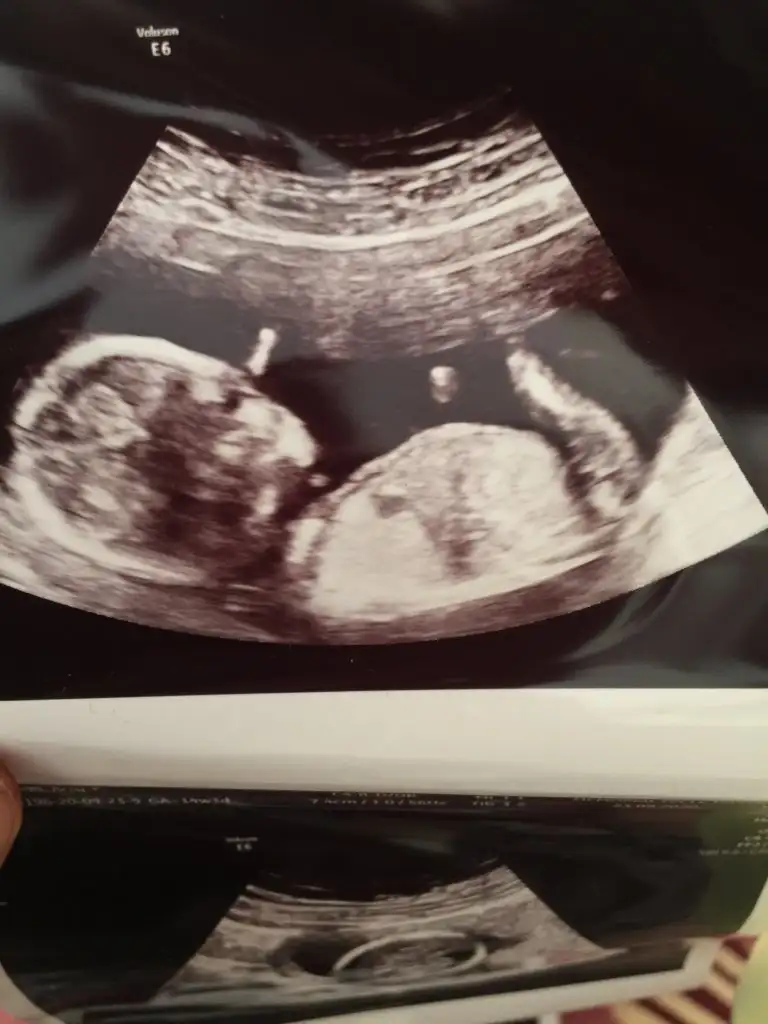

Evet erkek tahminim

Yok nuba iyi bakarsan dik ve parlak cnm Dr da erkek demisKız gibi

Erkek gibi ama tekrar USG istiyorumSelamIkra meyra banada yorum yapabilirmisin 11+3 teyiz Ikra meyra

USG 12.3 şimdi 17 haftalikGerçekten kaç haftalıkmış ikracım bu bebiş

12 haftalığa göre çok net göstermiş masallahUSG 12.3 şimdi 17 haftalik